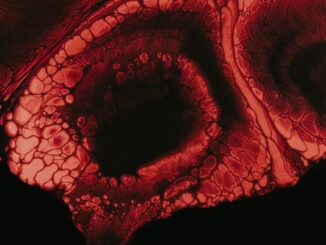

Revolutionizing Endoluminal Interventions

The Future is Now: Unpacking the Revolutionary Multiplexed Catheter-Integrated Pressure Sensing System In the relentless march of medical technology, where every millimeter and millisecond counts, innovation is more than just a buzzword; it’s the very […]